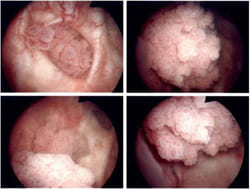

Цистоскопия: эндоскопическое исследование уретры и мочевого пузыря под наркозом. Позволяет на глаз обнаружить опухоль, оценить ее размеры, распространенность. Возможно взятие биопсии- кусочка опухоли для исследования.

Опухоль мочевого пузыря в виде «морской капусты» - цистоскопическая картина